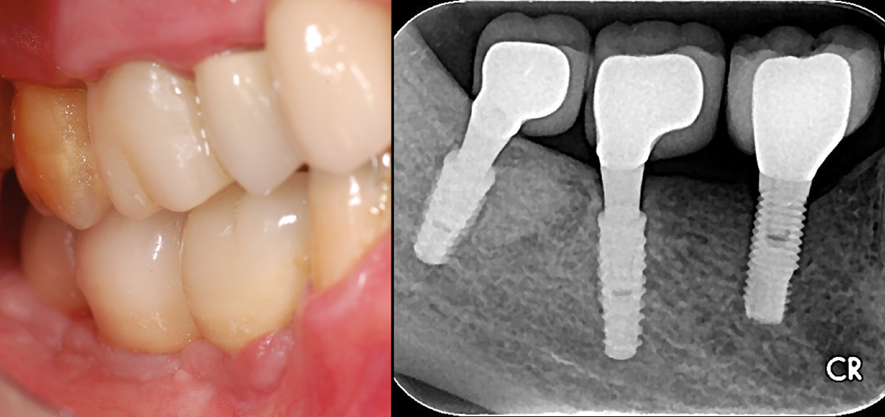

Figura 4 – Imagens clínica e radiográfica no controle de quatro anos após a colocação dos implantes. Observar a normalidade óssea peri-implantar e a boa incorporação do enxerto ósseo (Extra Graft – Implacil Osstem – São Paulo – Brasil).